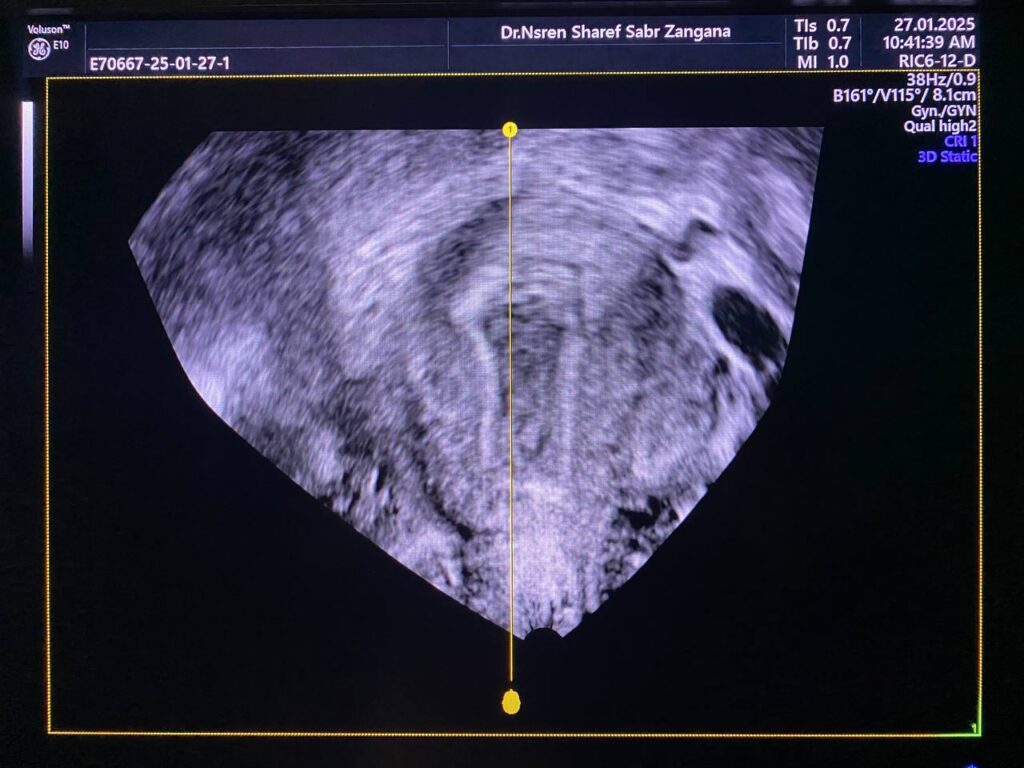

Heterogenous avascular endometrial thickening ( blood clot?) with Presence of hypoechoic vascular (score 4 ) mass within the distal part of the cervix (at level of external os), it’s size 15x15mm , its arise ( single pedicle vascular ) from upper cervical canal nearly (at level of internal os) , mostly pedunculated submucosal fibroid ? polyp? other cervical mass